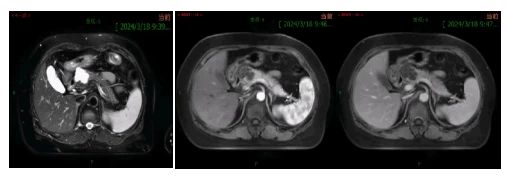

一般情况:女性,59岁。患者半天前于外院查胸部CT:胰头部占位,不伴有腹部疼痛。未行特殊治疗。既往高血压病史5年、Ⅱ型糖尿病病史5年。

肿瘤标志物:CA-199 11.7U/ml,CEA 0.80ng/ml,甲胎蛋白 3.76ng/ml。

手术方式:机器人辅助-腹腔镜下胰颈部肿物切除术+胰腺空肠吻合术。

传统的胰腺颈部肿瘤的手术类型主要有以下几种:胰十二指肠切除术、胰体尾切除术+脾切除术、全胰切除术。手术缺点则是过多切除胰腺组织,会导致胰腺内外分泌功能障碍,部分患者胰腺功能受影响较大,需要长期口服胰酶制剂和糖尿病药物,并且消化道重建会带来消化功能障碍、反流性胆管炎等问题,影响患者生活质量。因此,更多保留胰腺组织功能的手术应运而生-胰腺中段切除术(central pancreatectomy, CP)。随着胰腺外科微创技术的发展,腹腔镜胰腺中段切除术(laparoscopic central pancreatectomy, LCP)在大的胰腺中心已经开展。胰腺中段切除术操作难度大,肿瘤常紧邻脾动脉、静脉,手术时易损伤脾脏的血管,导致大出血。根据中国胰腺囊性肿瘤诊疗指南以及综合考虑患者病情,经科室主任及治疗小组讨论后一致决定,拟行机器人辅助-腹腔镜胰颈肿瘤切除术。